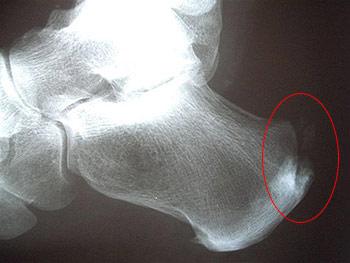

שינויים בעצם בזמן דלקת בגיד אכילס